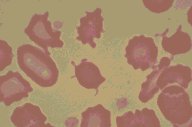

Spur cells and burr cells

Striking burr and spur cell abnormalities are seen in this high

oil magnification view of the Wright's stained peripheral blood

in a patient with hepatorenal failure. Generally, the bur cells or

echinocytes have a more even distribution over the surface of the

red blood cell. The spur cells have a smaller number of projections

on a stalk.